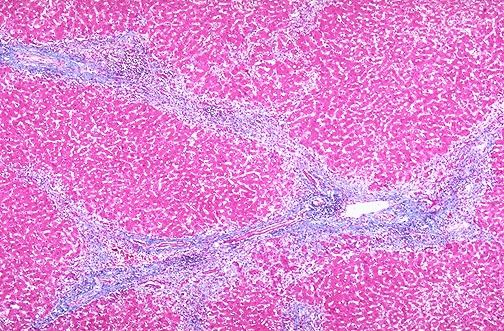

This trichrome stain demonstrates the collapse of the liver parenchyma with viral hepatitis. The blue-staining areas are the connective tissue of many portal tracts that have collapsed together.